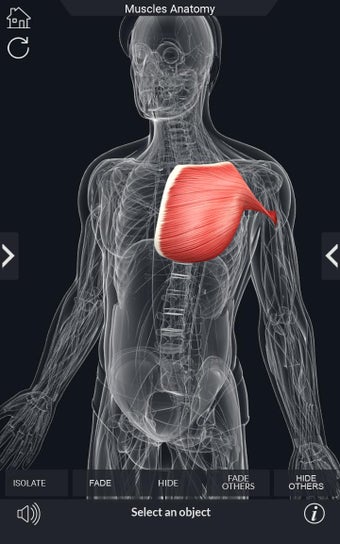

Den mest omfattande mobilappen som finns i världen för att studera muskelanatomi, som låter dig rotera 360°, zooma och flytta kameran runt en mycket realistisk 3D-modell.

Det finns många verktyg tillgängliga för varje muskel, inklusive:

- Göm och visa varje muskel separat.

- Rotera 360°.

- Zooma in och ut.

- Flytta kameran runt modellen.